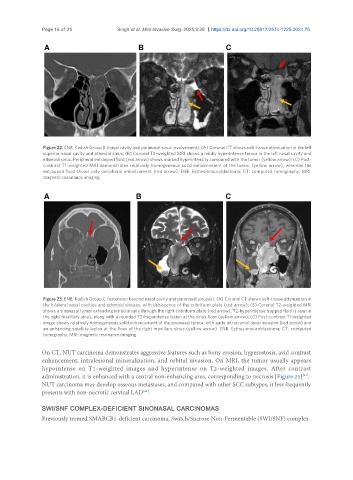

Figure 22. ENB, Kadish Group B (nasal cavity and paranasal sinus involvement). (A) Coronal CT shows soft-tissue attenuation in the left

superior nasal cavity and ethmoid sinus; (B) Coronal T2-weighted MRI shows a mildly hyperintense tumor in the left nasal cavity and

ethmoid sinus. Peripheral entrapped fluid (red arrow) shows marked hyperintensity compared with the tumor (yellow arrow); (C) Post-

contrast T1-weighted MRI demonstrates relatively homogeneous solid enhancement of the tumor (yellow arrow), whereas the

entrapped fluid shows only peripheral enhancement (red arrow). ENB: Esthesioneuroblastoma; CT: computed tomography; MRI:

magnetic resonance imaging.

Figure 23. ENB, Kadish Group C (extension beyond nasal cavity and paranasal sinuses). (A) Coronal CT shows soft-tissue attenuation in

the bilateral nasal cavities and ethmoid sinuses, with dehiscence of the cribriform plate (red arrow); (B) Coronal T2-weighted MRI

shows a sinonasal tumor extending intracranially through the right cribriform plate (red arrow). T2-hyperintense trapped fluid is seen in

the right maxillary sinus, along with a rounded T2-hypointense lesion at the sinus floor (yellow arrow); (C) Post-contrast T1-weighted

image shows relatively homogeneous solid enhancement of the sinonasal tumor, with early intracranial dural invasion (red arrow) and

an enhancing satellite lesion at the floor of the right maxillary sinus (yellow arrow). ENB: Esthesioneuroblastoma; CT: computed

tomography; MRI: magnetic resonance imaging.